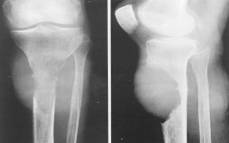

GONARTROZA se întâlneste mai frecvent la femei, dupa menopauza. Este secundara când apare dupa leziuni preexistente: genum valgum, varum, luxatie congenitala de sold, traumatisme ale genunchiului.

Radiologic: reducerea spatiului articular si osteofite. Ele se evidentiaza pe radiografia de profil. La nivelul articulatiei femuro-tibiale se evidentiaza pensarea inegala a articulatiei, derotunjirea suprafetelor articulare, largirea si alungirea spinelor tibiale prin osteofite, scleroza suprafetelor articulare, aparitia de formatiuni pseudochistice în platourile tibiale, osteofite.